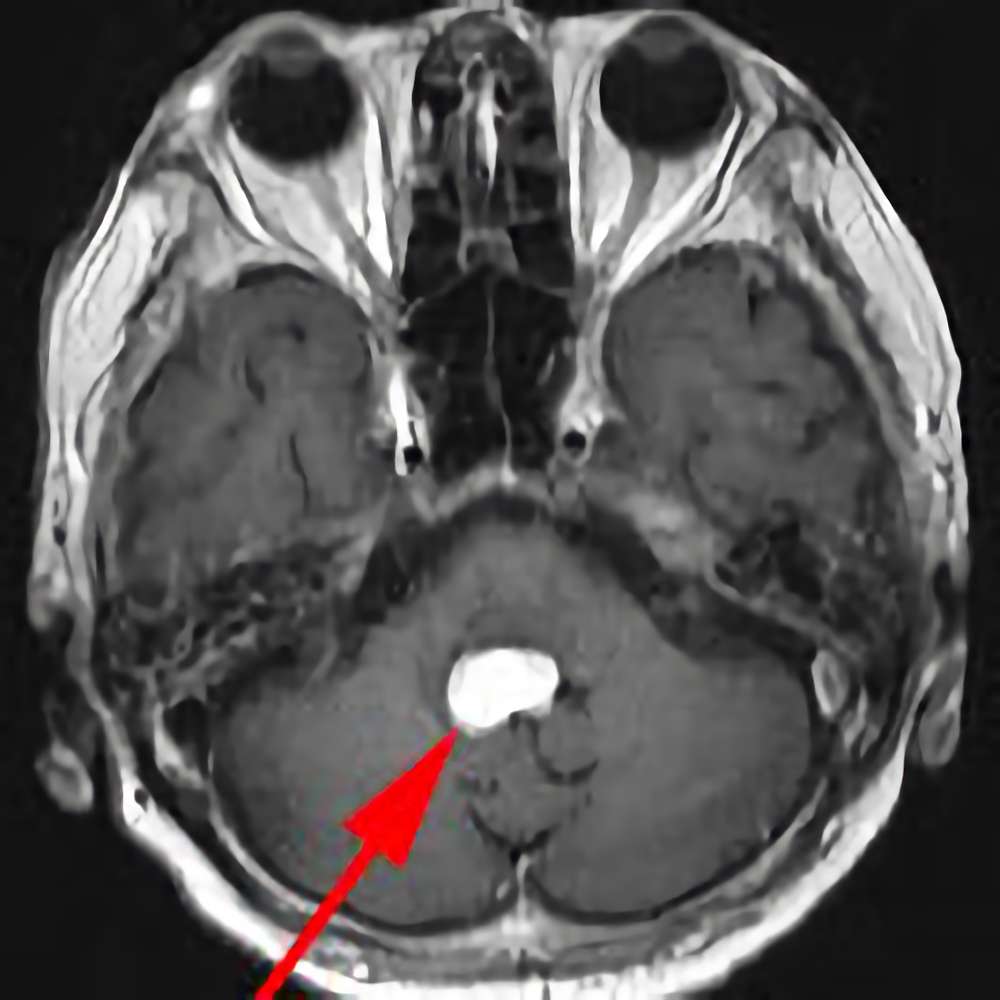

183

'21年6月

50代

小脳血管芽腫

頭蓋内腫瘍摘出術

No.’21_27 手術前1

No.’21_27 手術前2

No.’21_27 摘出 前

No.’21_27  摘出 中

No.’21_27 摘出 後